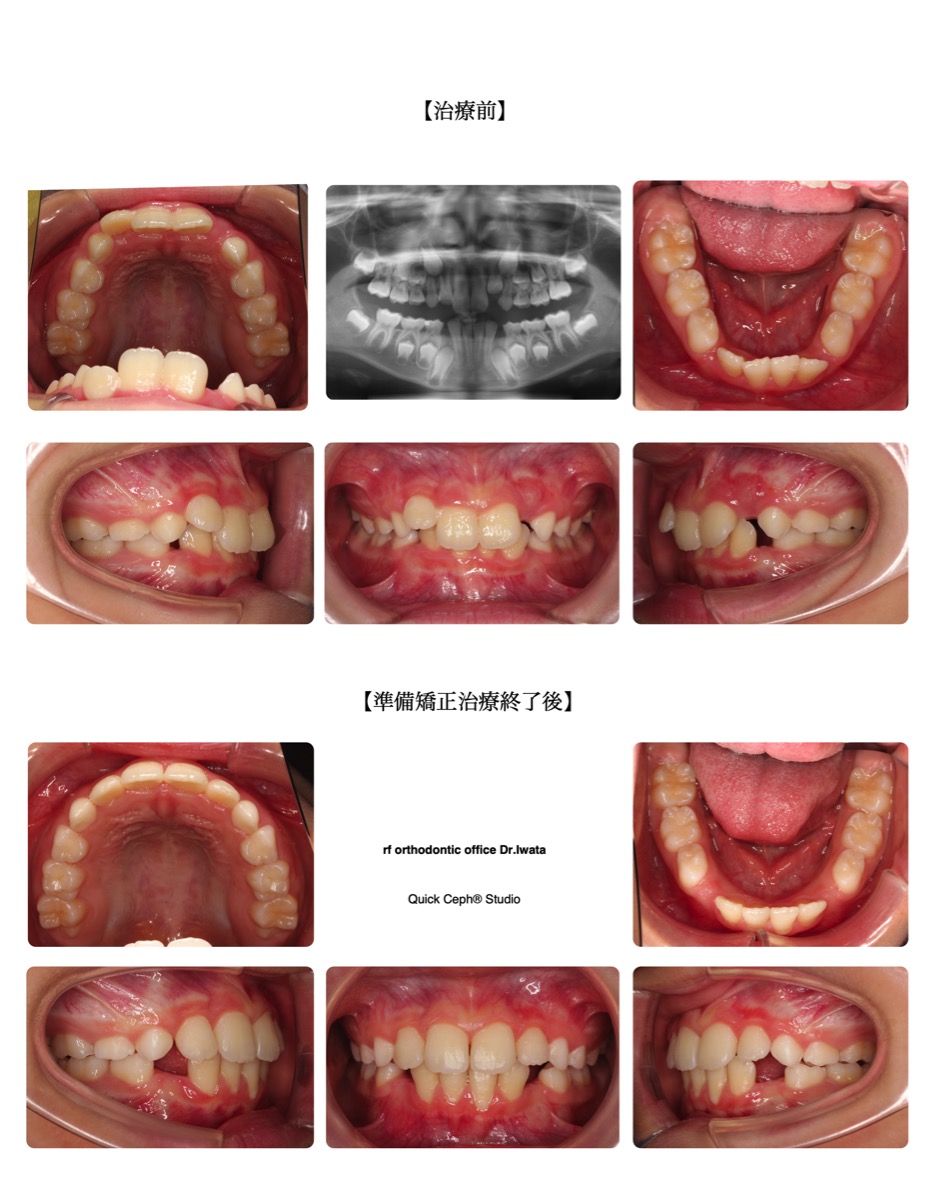

【主訴】かみ合わせが深く、上の前歯が変な向きで生えてきた。下の乳犬歯も結構前に抜けたが永久歯がなかなか生…